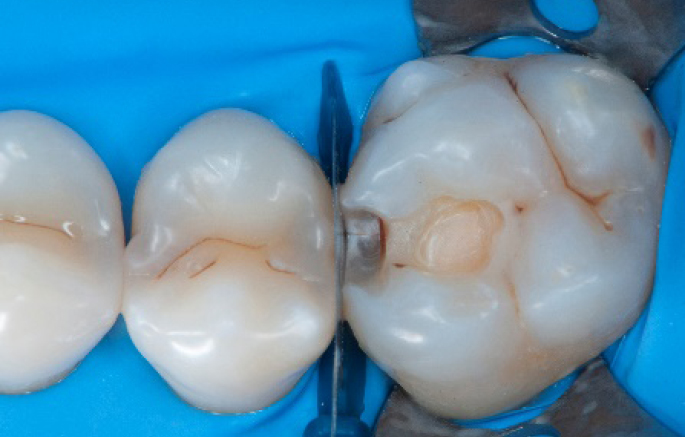

Step 3:

Class II cavity prepared.

Step 4:

The complete Palodent1 system in place: sectional matrix, wedge and ring.